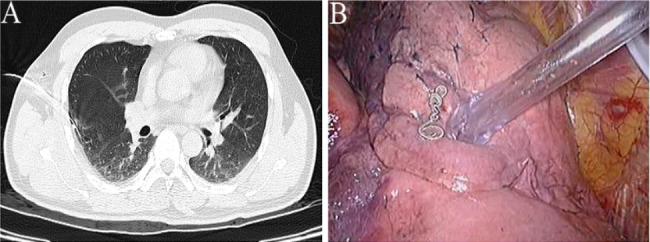

This is a retrospective study of adverse events associated with preoperative computed tomography (CT)-guided hookwire or coil localisation. We analysed the experience and process flaws in resecting ground-glass nodules (GGNs) through video-assisted thoracoscopic surgery (VATS) and determined the remedial strategy.

Adverse events were evaluated in 40 patients with 45 GGNs who underwent CT-guided hookwire or coil localisation before VATS. For lesions not successfully marked or detected, palpation, resection of the highly suspected area, segmentectomy or lobectomy was performed.

Among all adverse events, 15 were dislodgement of the marking materials, 5 were breakaway of the marking materials, 7 were > 2 cm distance between the lesions and the tips, 3 was marking material across the two adjacent lobes, 15 were pneumothorax and 2 were certain parts of marking materials stuck into the chest wall. All GGNs were resected successfully. 20 lesions were detected by palpation. 9 GGNs were discovered after the resection of highly suspected areas. Segmentectomies and lobectomies were performed directly on 7 and 9 GGNs, respectively.

When adverse events occur, a second intraoperative localisation, by resecting the highly suspected area either through non-anatomical resection (wedge resection) or anatomical resection (segmentectomy or lobectomy) using the VATS should be considered the alternatives for GGNs localization.